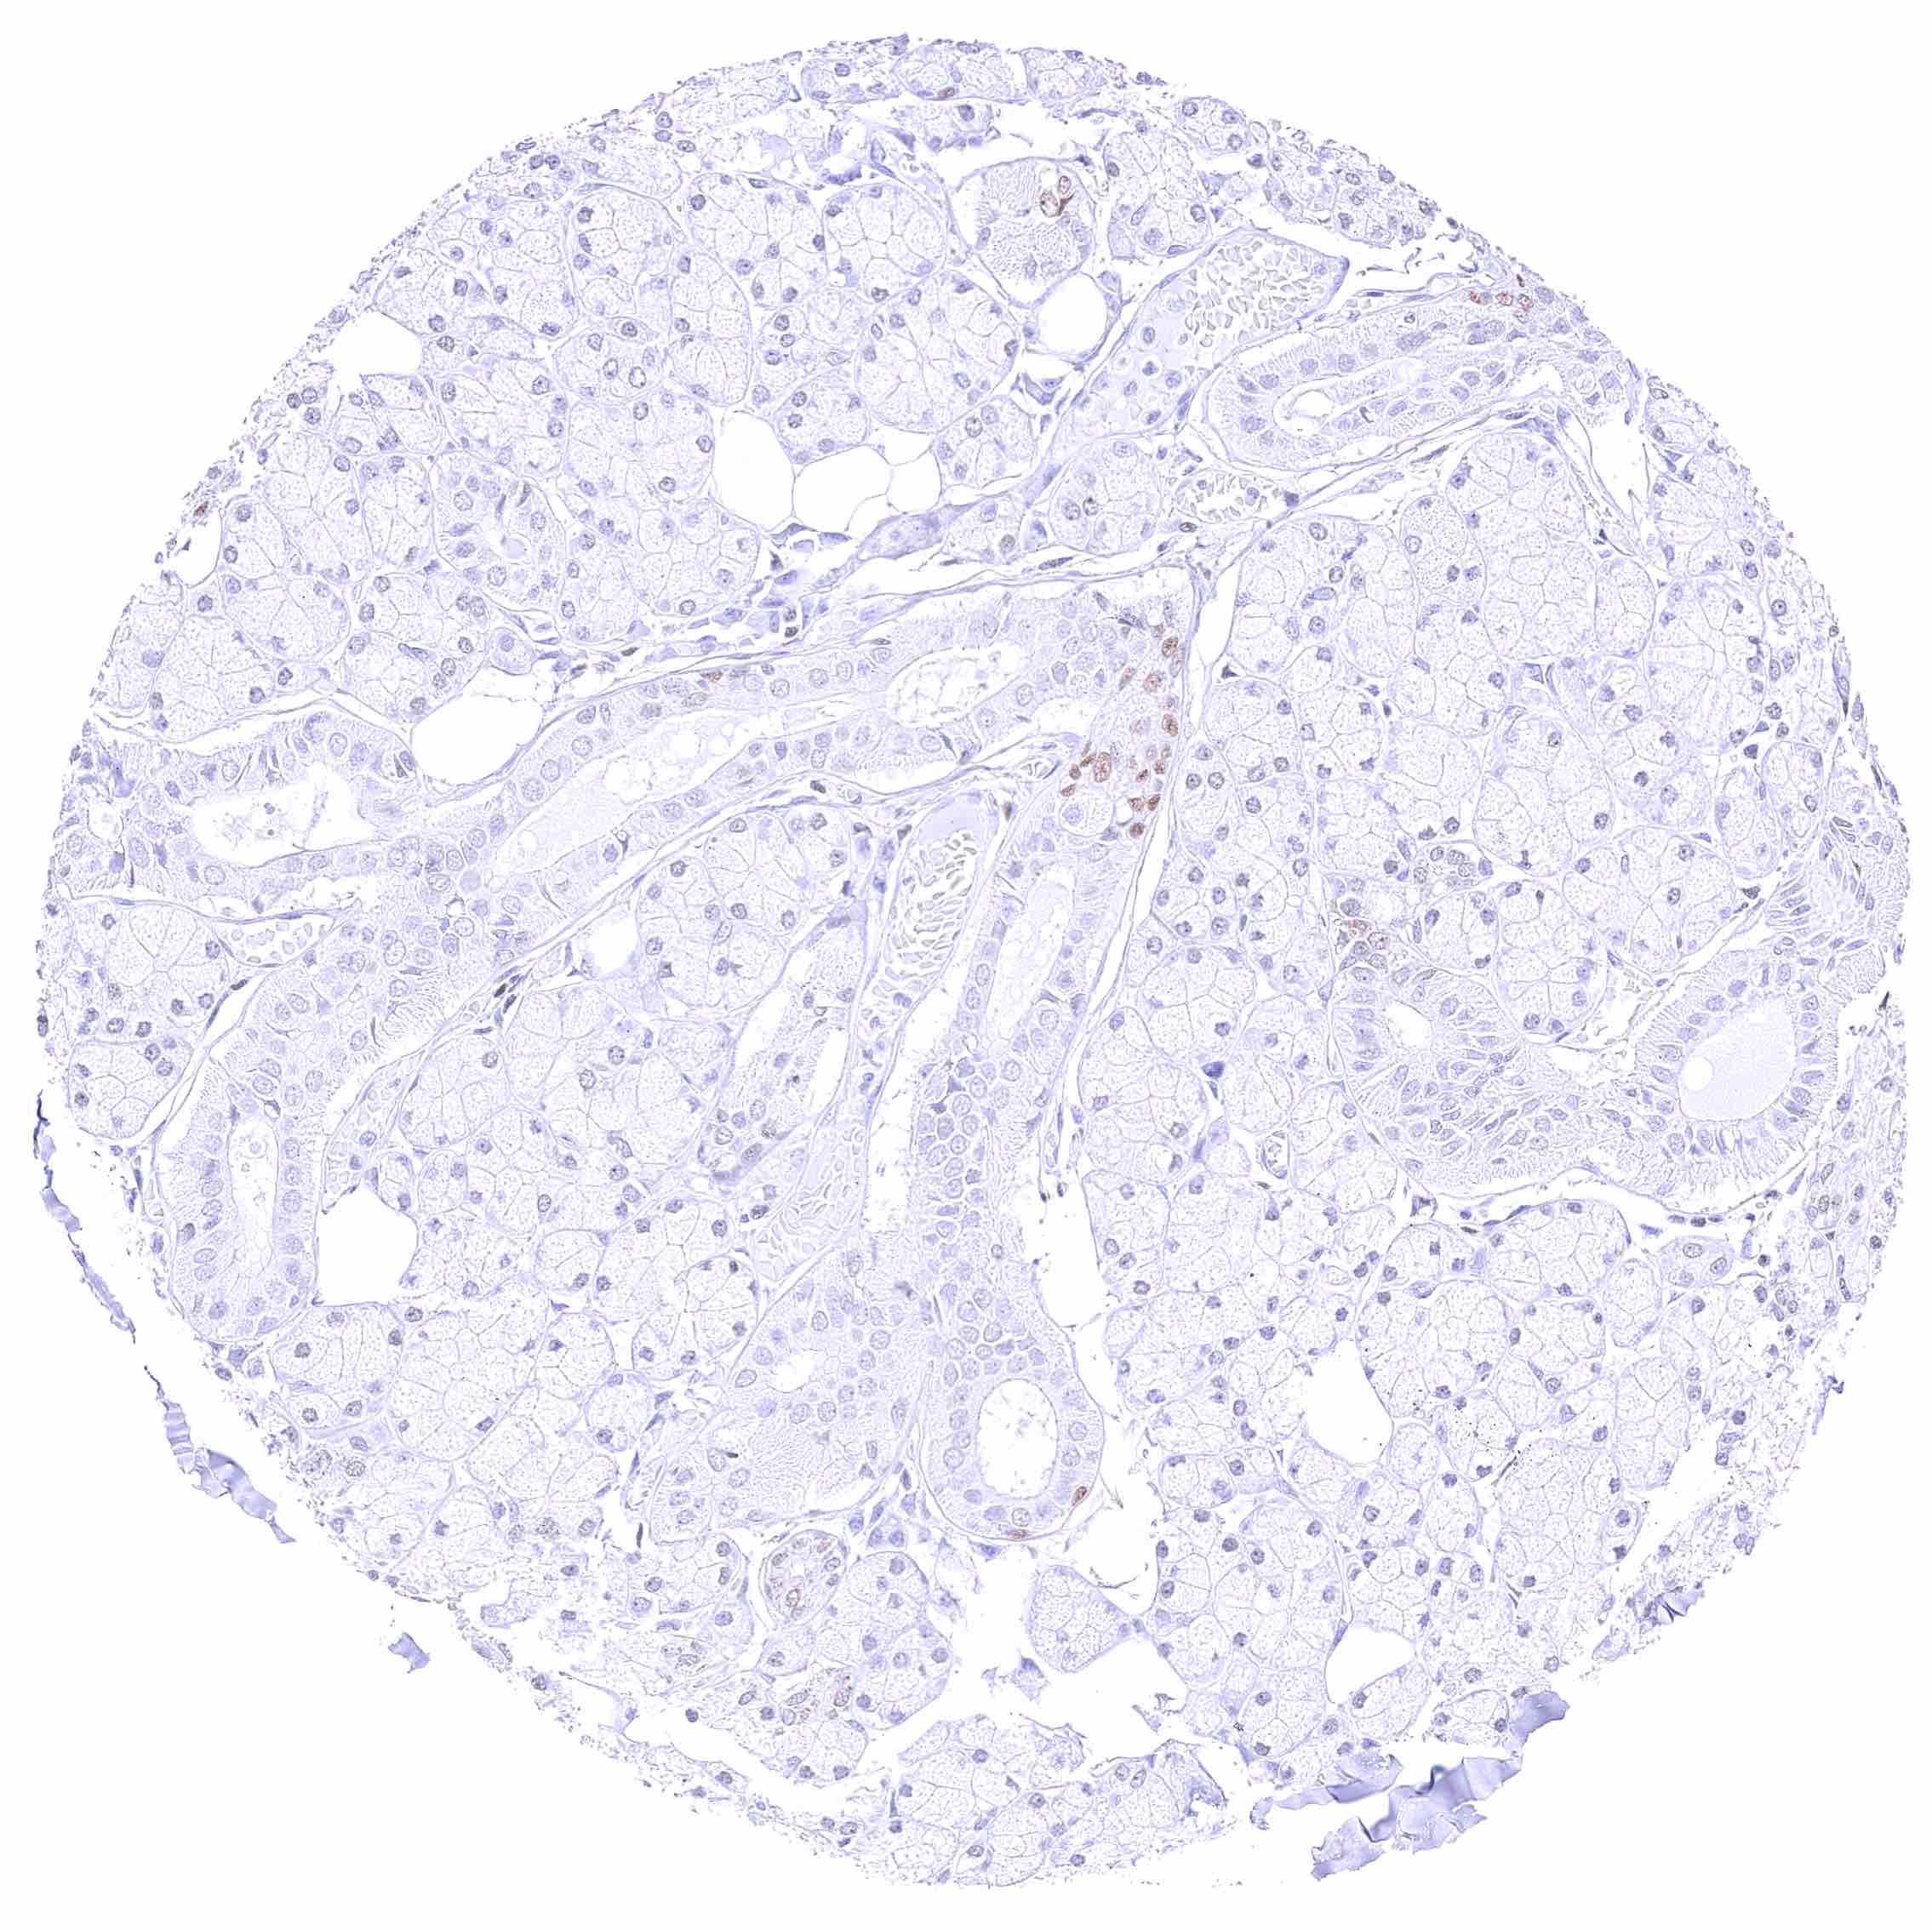

Kidney, cortex – Moderate to strong, nuclear GATA3 positivity of collecting ducts, some cells of distal tubuli, and of podocytes.

Kidney, medulla – Moderate to strong, nuclear GATA3 positivity of some collecting ducts.

Kidney, pelvis, urothelium – Strong nuclear GATA3 positivity of all urothelial cells.